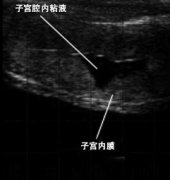

吉彩网牛用B超什么时候检测母牛是否怀孕? 母牛配种之后很多人不知道是否配上种,牛用B超机是判断母牛是否怀孕的超声设备,判断母牛是否怀孕,可以通过B超影像子宫的状态来进行分析。……